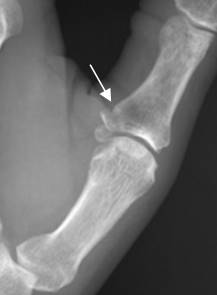

Fig 168. Dedo en martillo.

A: Rx lateral. Avulsión sobre la inserción del tendón extensor, en la base en la falange distal.

B: RM sagital en T1. Se confirma la avulsión. El tendón extensor se aprecia íntegro.